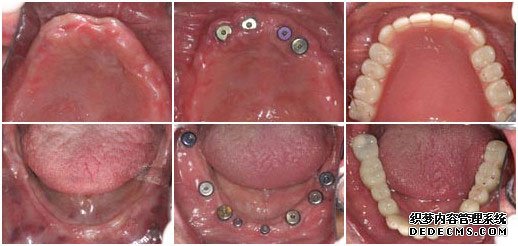

种植牙前 植入种植体后 套上烤瓷牙冠完成手术

检查:全口牙齿缺失,无能明显依托的牙根,X片显示根尖无异常

美牙方案:通过口腔数码内窥镜、口腔全景机及微创无痛设备,精密观测口腔内的状况,运用先进的瑞士ITI种植牙技术进行种植。

美牙后:全口牙修复成功,恢复了咀嚼功能,饮食和说话都能自如。

王老伯来武汉爱齿尔口腔就诊的时候,情况非常糟糕,在医生的检查下,发现他口腔内的牙齿全部缺失,并没有可持久依托的牙根,面对这一情况,医生只有建议王老伯做种植牙。虽说种植牙的治疗时间较长,但是对于王老伯这样的牙齿状况,种植牙是一种十分理想的选择。

由于王老伯今年已经61岁,所以在植入种植体后的恢复时间比一般人要常一些,花了将近5个月的时间才长好,但这并不影响种植牙的效果。最后在套烤瓷牙冠的时候,王老伯的家人也感到十分惊异,因为种出来的牙齿不但美观漂亮,甚至比王老伯之前的真牙还要逼真,一下子王老伯的牙齿看起来仿佛只有20多岁。而最最高兴的还是王老伯,他说:“我以前戴的全口活动假牙,吃东西不方便,连老伴弄的饭菜也都不想吃,可这次种牙太成功了,真是那句老话:‘牙好,胃口就好啊!’,太感谢你们了”